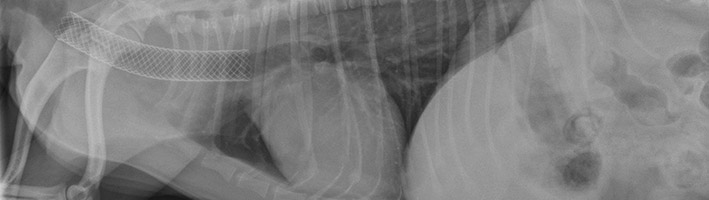

- Interventional Tracheal Stenting

- Interventional Urethral Stenting